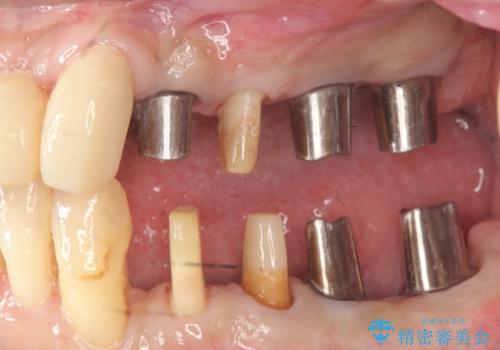

- 歯が全体的に揺れ始め、恐怖を感じ他院に相談に行ったところ、全体的な歯周病の問題・抜歯の必要性・入れ歯の提案を受け、入れ歯以外の選択肢を希望され来院されました。

全体的な歯周病検査を行い、多数の残すことのできない抜歯の必要な歯を認めたため、残せる歯に対しての徹底的な歯周病治療、失った歯に対しブリッジ・インプラント治療を全顎的に行っていくこととしました。